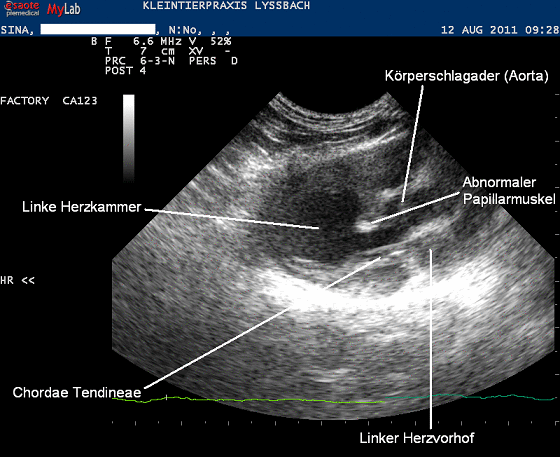

Im Herzultraschall wird schlussendlich ersichtlich, was bei der Katze das beobachtete Herzgeräusch verursacht:

Offenbar weist das Herz von Sina eine Missbildung auf. Während in einem normalen Herzen (wie oben beschrieben) das Herzseptum in der linken Kammer keinen Papillarmuskel trägt, entspringt bei Sina einer der beiden Muskeln der Herzscheidewand, währenddem der andere normal ausgebildet wird (in der Grafik rot eingezeichnet). Zwar scheint der Verschluss der Mitral-Segelklappen trotzdem normal zu funktionieren, jedenfalls ist während der Pumpaktion des Herzens kein Blutrückfluss in den Vorhof zu beobachten. Die abnormal verlaufenden Chordae Tendineae und der abnormal ausgebildete Papillarmuskel ragen aber in die Kammerregion hinein, durch welche das Blut in die Körperschlagader (Aorta) gepumpt wird.

Glücklicherweise scheint dies für das Herz vorerst keinen grossen Nachteil darzustellen: Die Abmessungen von Herzmuskel und Kammerdurchmessern erscheinen normal, offenbar hat das Herz bis jetzt nicht negativ auf die abnormale Anatomie reagiert.

Glücklicherweise scheinen sich solche Sekundärveränderungen bei "Sina" bis heute nicht eingestellt zu haben. Da kein Blutrückfluss in den linken Vorhof und keine Vorhoferweiterung festgestellt werden konnte, ist anzunehmen, dass das gehörte Geräusch durch die Positionierung des abnormalen Papillarmuskels im Ausflusstrakt der Aorta zustande kommt.